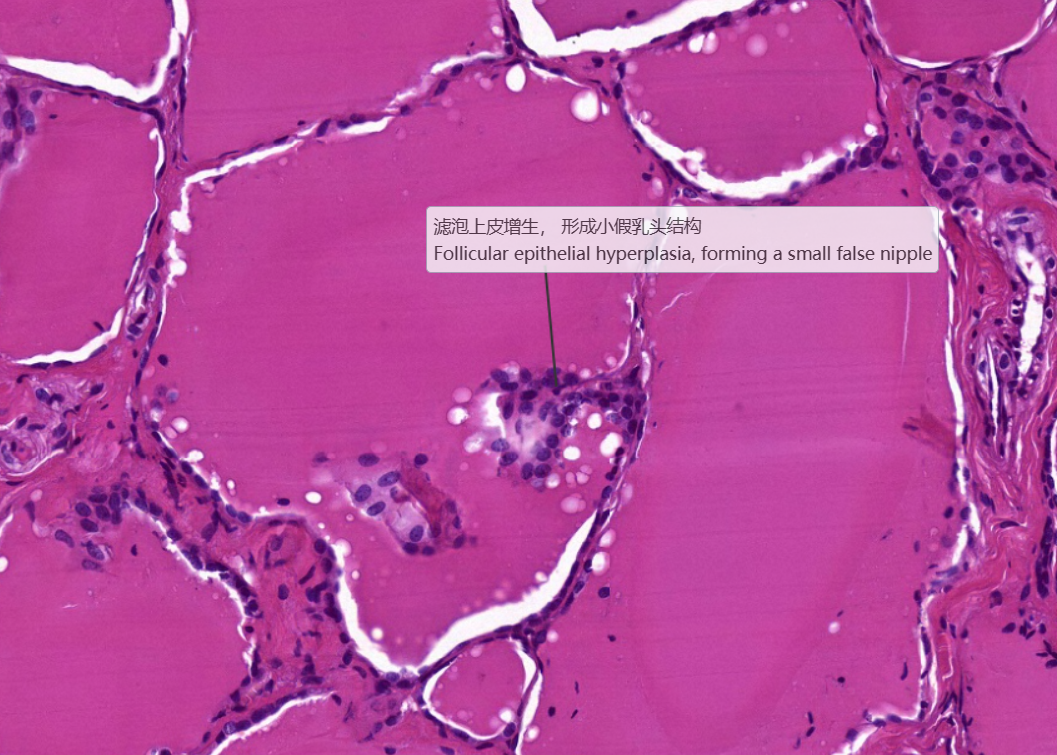

弥漫性非毒性甲状腺肿:甲状腺滤泡明显扩张,内含大量胶质,滤泡上皮细胞受压呈扁平状。部分上皮增生,可见小滤泡和小假乳头形成。

3.滤泡上皮增生

4.滤泡扩张